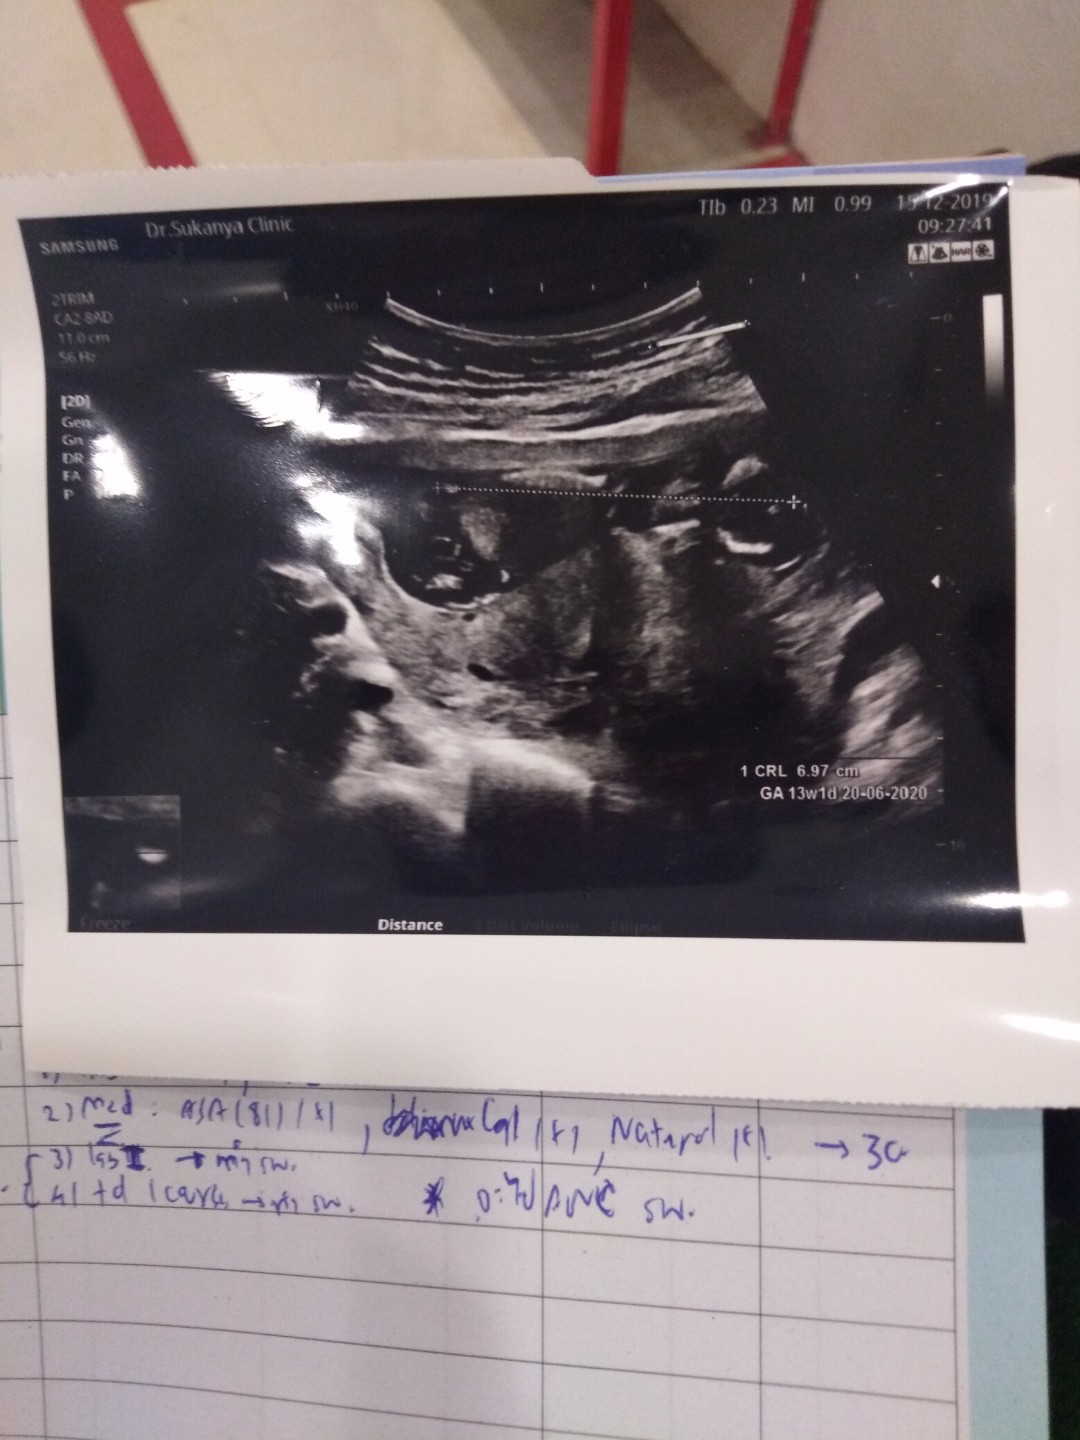

13 week จ้า